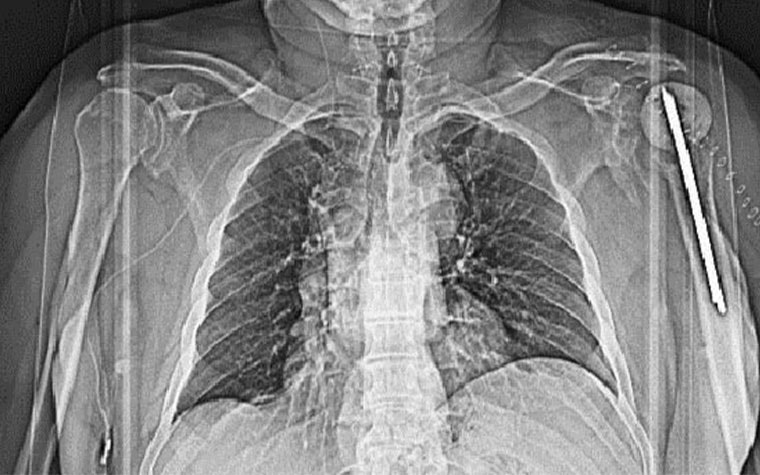

Left: Pre-op X-ray showing the old implant in the patient’s left shoulder. Right: Prof. Dr. Stefaan Nijs, Chairman of Trauma Surgery at Leuven University Hospital